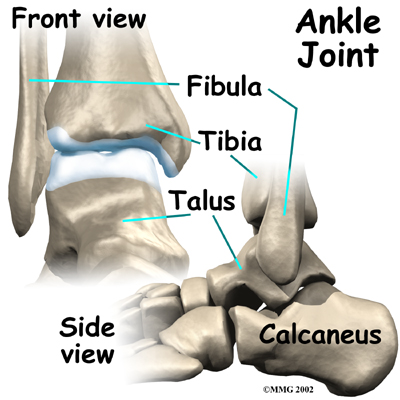

The ankle joint is made up of three bones: the lower end of the tibia (shinbone), the fibula (the small bone of the lower leg), and the talus (the bone that fits into the socket formed by the tibia and fibula). The talus sits on top of the calcaneus (the heelbone).

The talus moves mainly in one direction. It works like a hinge to allow your foot to move up and down.

Ligaments on both sides of the ankle joint help hold the bones together. Many tendons cross the ankle to move the ankle and the toes. (Ligaments connect bone to bone, while tendons connect muscle to bone.)